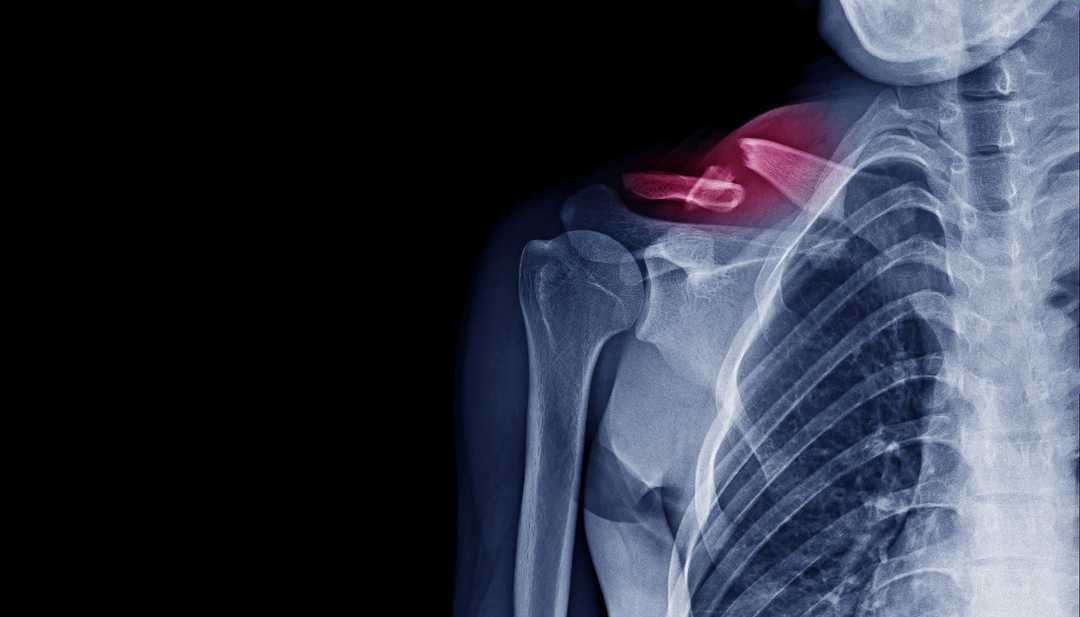

Clavicule Cassee Temps Guerison . Dans cet article nous ajoutons des précisions sur la durée. La reprise du sport peut être plus longue. ⏱️ temps de guérison et récupération après une fracture de la clavicule. la durée varie en fonction de plusieurs facteurs, peut aller de 6 à 12 semaines (3 mois). Toutefois, si votre clavicule a été déplacée ou nécessite une intervention chirurgicale pour être réparée, la période de récupération peut être beaucoup plus longue et nécessiter des soins complémentaires. La douleur diminue en général assez rapidement au repos, mais peut durer plusieurs semaines lors des mouvements de l’épaule. L’immobilisation de la clavicule dure selon le type de fracture de 3 à 6 semaines. en général, il faut bien 6 à 10 semaines pour guérir d’une clavicule cassée. Tous ces délais sont raccourcis chez l’enfant et l’adolescent. le temps de guérison d’une clavicule cassé est d’environ 6 semaines. la fracture de la clavicule est une cassure du long os qui est horizontale entre la partie supérieure du sternum et la partie supérieure de l’omoplate. 🚭 comment maximiser les chances de consolider vite et bien ?

la durée varie en fonction de plusieurs facteurs, peut aller de 6 à 12 semaines (3 mois). 🚭 comment maximiser les chances de consolider vite et bien ? en général, il faut bien 6 à 10 semaines pour guérir d’une clavicule cassée. La reprise du sport peut être plus longue. Toutefois, si votre clavicule a été déplacée ou nécessite une intervention chirurgicale pour être réparée, la période de récupération peut être beaucoup plus longue et nécessiter des soins complémentaires. ⏱️ temps de guérison et récupération après une fracture de la clavicule. le temps de guérison d’une clavicule cassé est d’environ 6 semaines. Tous ces délais sont raccourcis chez l’enfant et l’adolescent. L’immobilisation de la clavicule dure selon le type de fracture de 3 à 6 semaines. la fracture de la clavicule est une cassure du long os qui est horizontale entre la partie supérieure du sternum et la partie supérieure de l’omoplate.